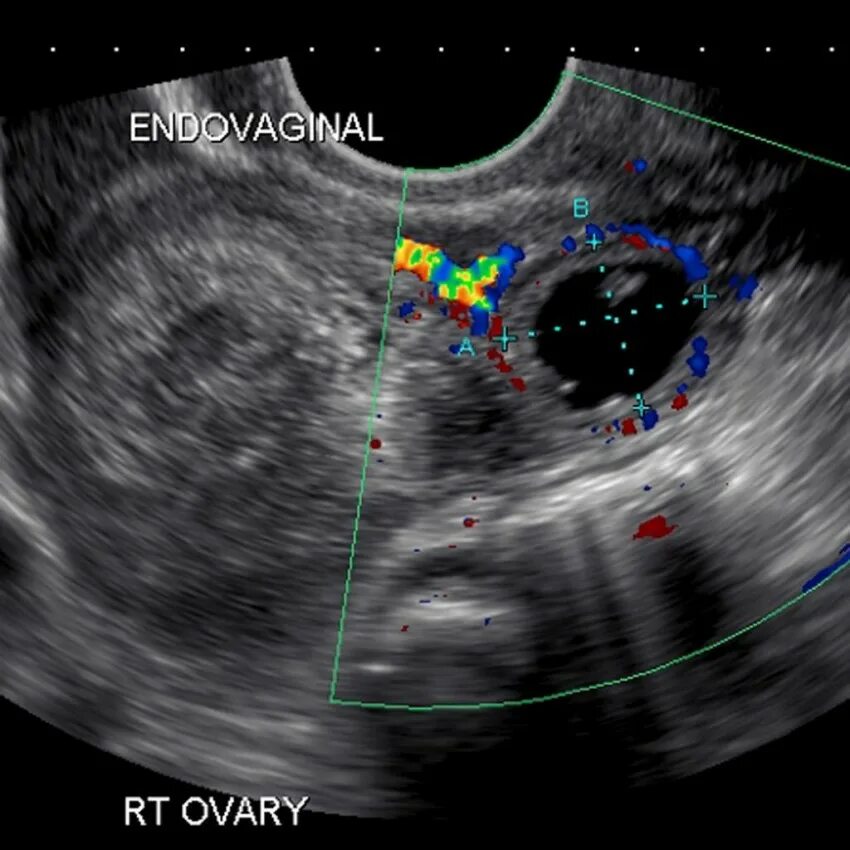

Можно ли на узи увидеть внематочную беременность